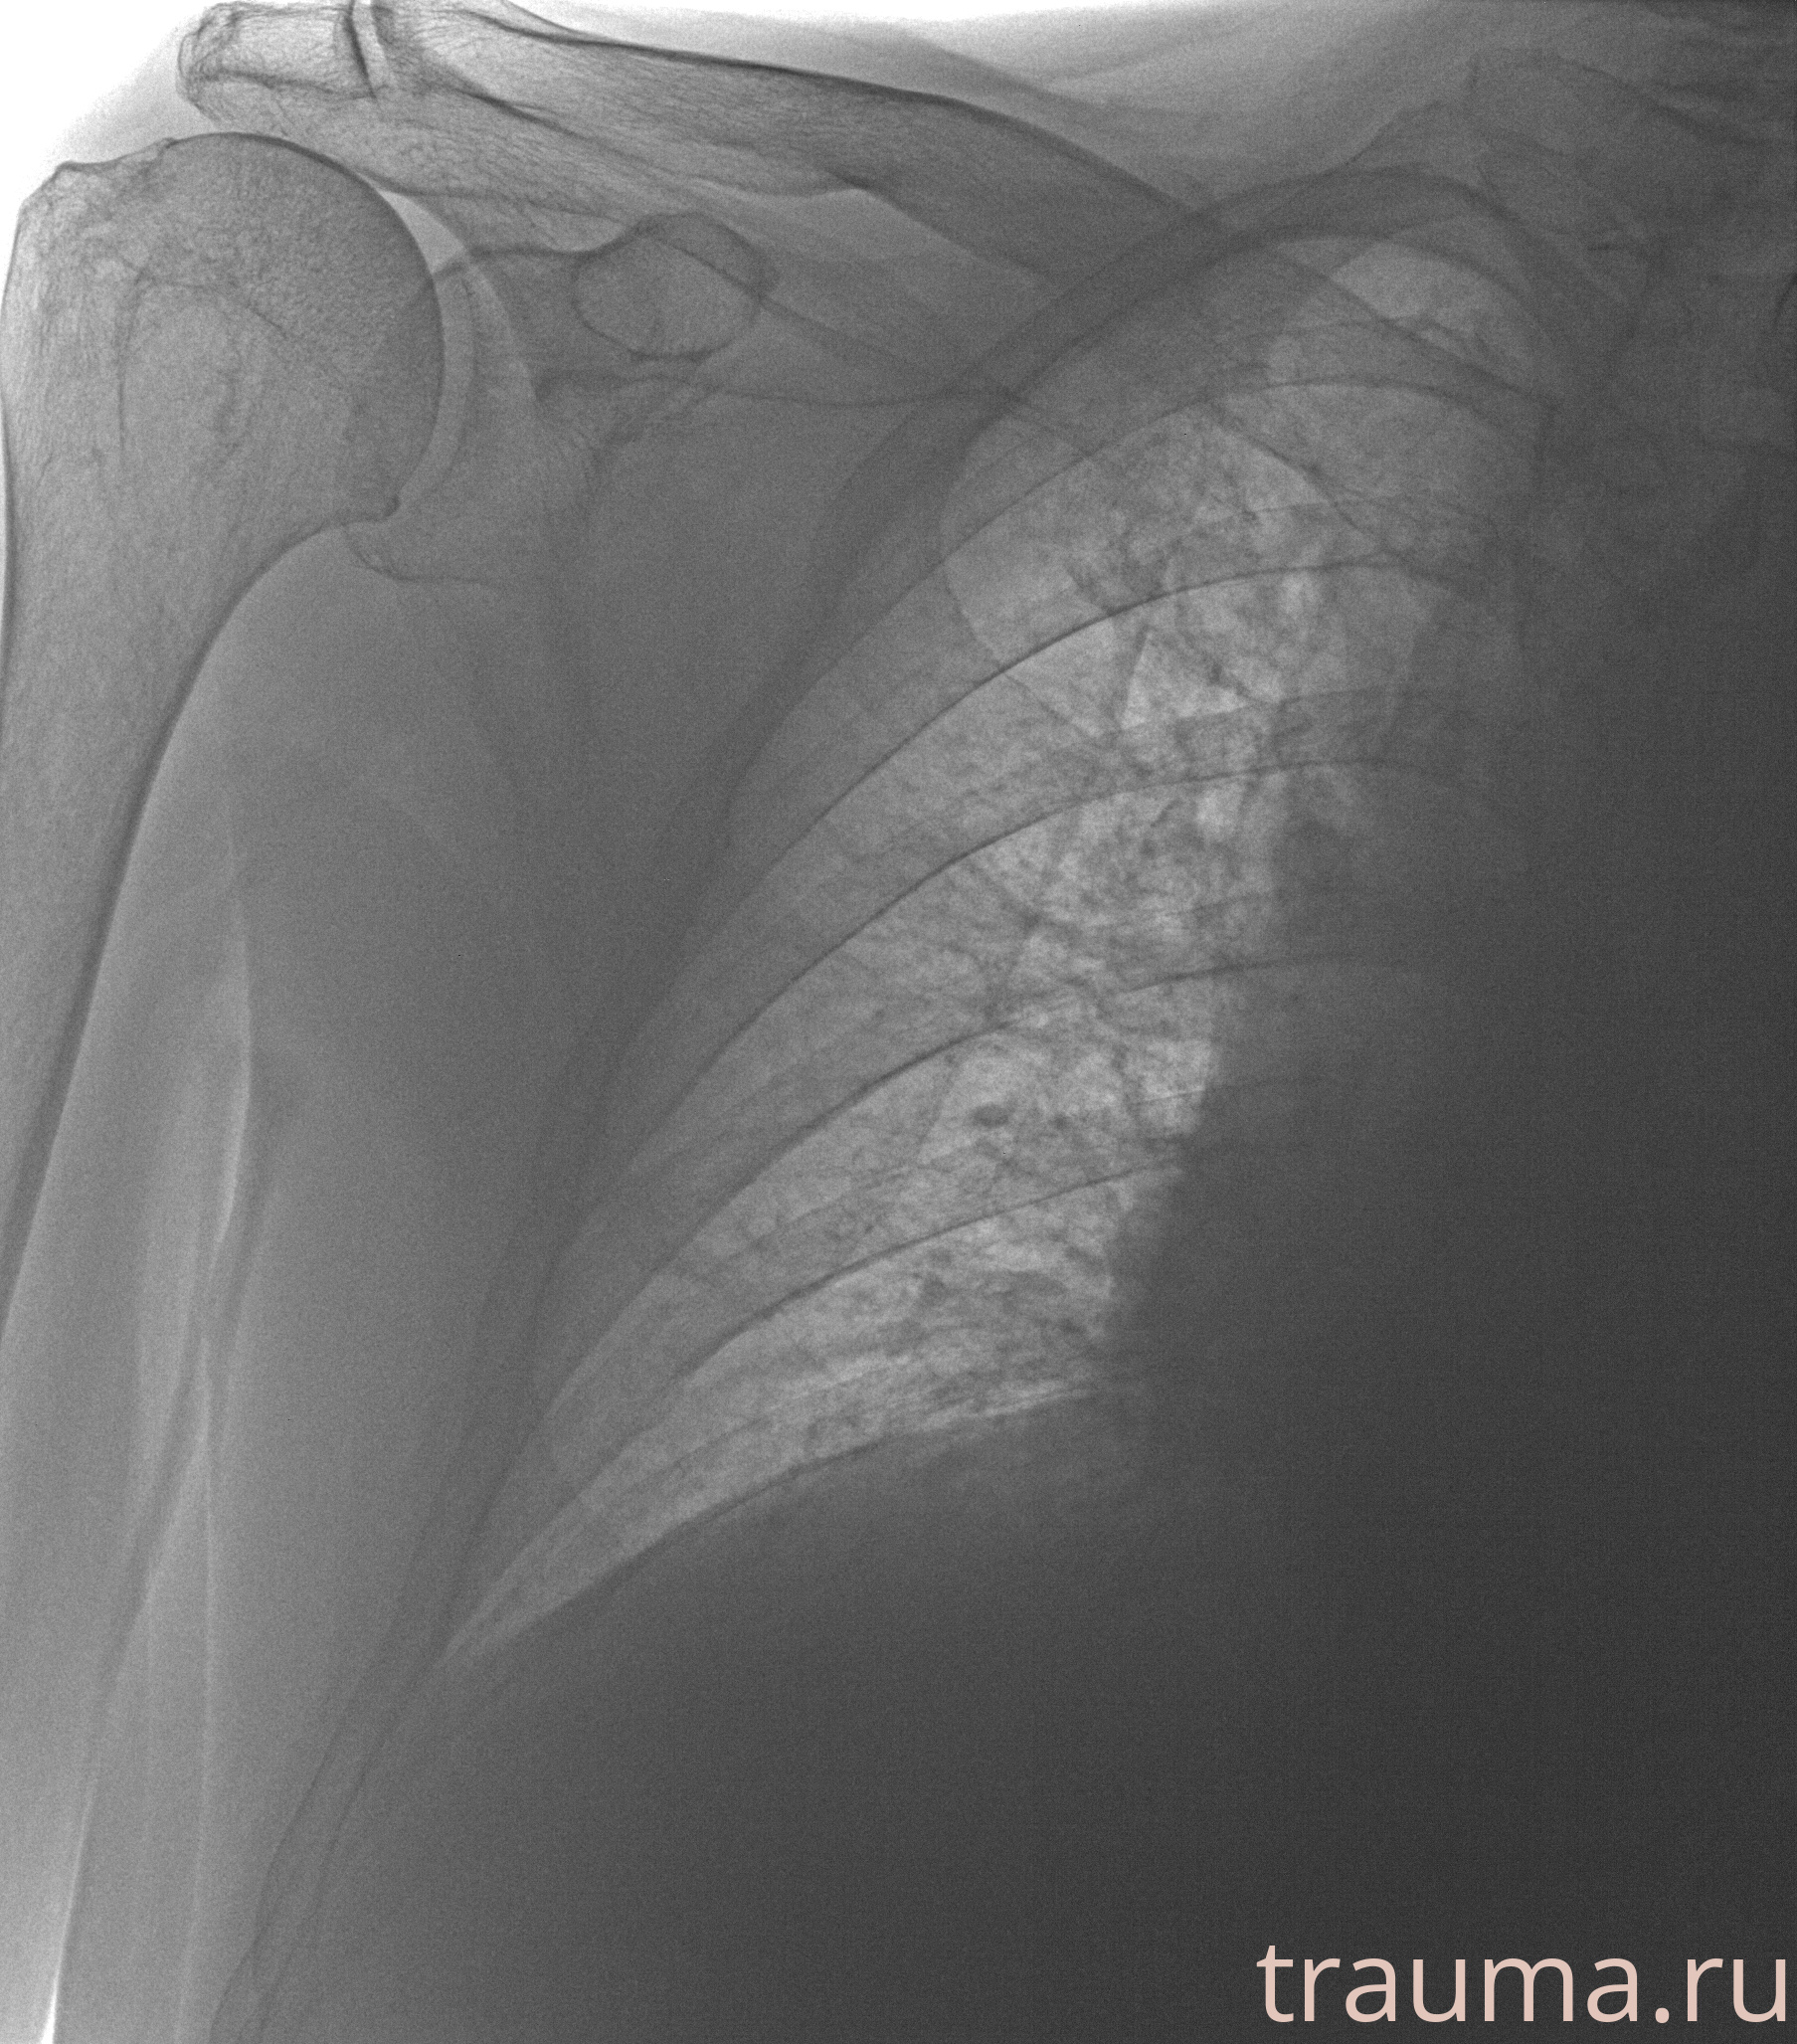

Рентгенограммы

Рентген на дому: по вашему адресу приезжает врач-рентгенолог, травматолог-ортопед с мобильным рентгеновским аппаратом, проводит диагностику травмы или заболевания, делает необходимые рентгенограммы, дает рекомендации по дальнейшему лечению. Получить качественные снимки в домашних условиях возможно благодаря уникальной методике, разработанной МосРентген Центром для института  Склифосовского